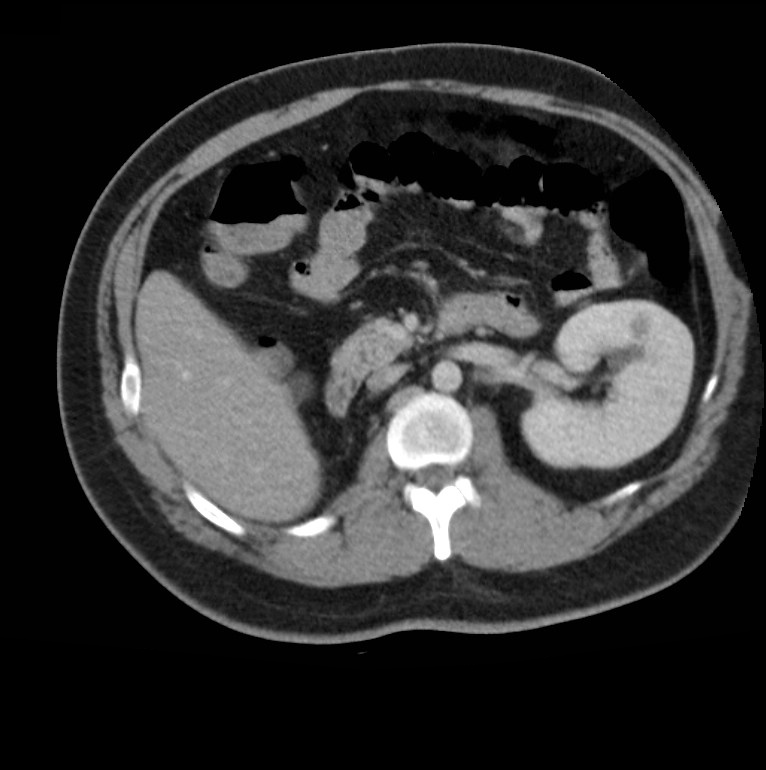

动脉粥样硬化肾结石形成突出显示的肾脏肾癌人体肾脏单肾横切面肾脏

孤立肾

先天性单肾